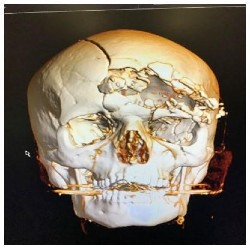

Fractures multiples du massif facial (reconstruction 3D par tomodensitométrie).